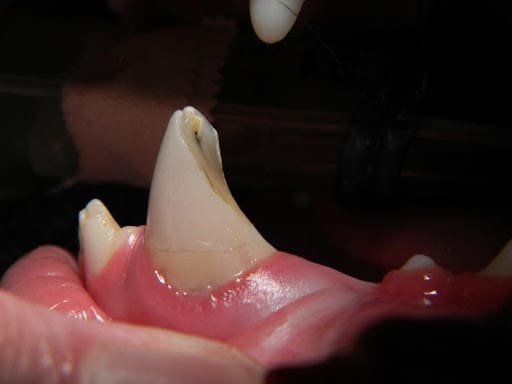

Restoration procedures involve repairing structural damage to the tooth that does not include pulp exposure. Common tooth pathologies requiring restoration procedures include carious lesions and enamel dentin fractures. In caries, also known as cavities, the carious tissue is removed, followed by placement of restoration material. This is important since without treatment the lesion will progress, leading to the eventual loss of the tooth. Enamel dentin fractures are commonly referred to as uncomplicated crown fractures that do not result in direct pulp exposure. An odontoplasty (smoothing) and bonded sealant procedure is used to treat these cases. The fractured site is smoothed, followed by the application of a dentin bonding agent and unfilled resin to protect the tooth. Crown fractures and caries are painful. When left untreated they will often lead to internal infection of the tooth causing even more pain.

Figure 3. A canine (fang) tooth in a dog with a painful and infected crown fracture with pulp exposure

Figure 4. The same tooth after root canal therapy and crown restoration was performed.